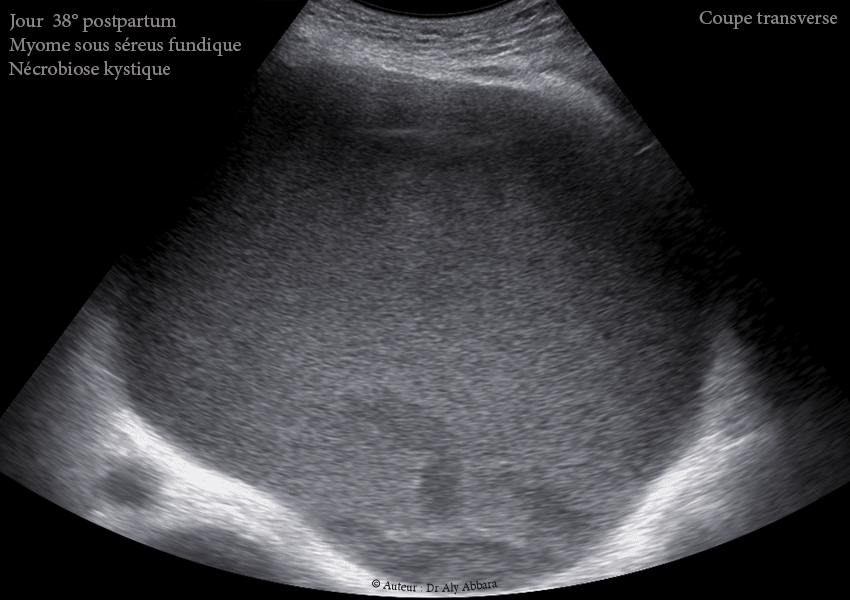

Images échographiques montrant un utérus myomateux portant un myome sous-séreux fundique (classe 7 de la classification FIGO 2011). Images prises au 38ème jour du postpartum après un accouchement par césarienne au terme de 36,5 SA.

Au 38ème jour du postpartum, ce myome apparaît comme une énorme formation kystique de 1200 cm3 de volume, vascularisée et attachée à la surface extérieure du fond utérin ; son contenu est trouble, liquidien, hypoéchogène avec des plages d'aspect nuageux liées à la présence de résidus flottants (nécrotiques).

Au jour 38 du postpartum : dégénérescence kystique quasi totale ; décroissance volumique (1200 ml).